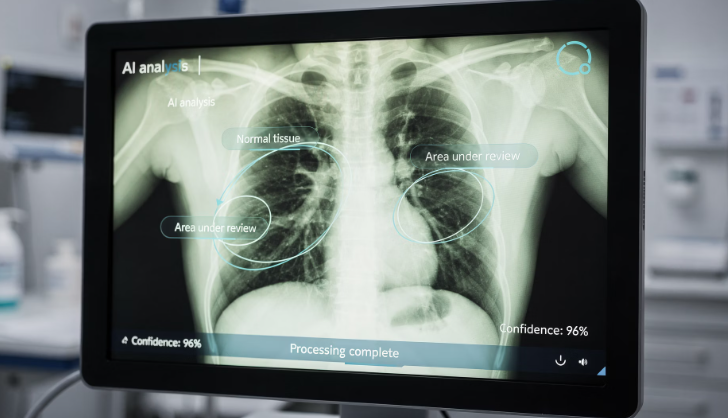

실제 익명화된 흉부 X-ray 데이터나 심전도 데이터를 활용해 진단 보조 모델을 직접 구동해 보는 과정이 필요합니다. 2026년에는 코딩을 몰라도 사용 가능한 '노코드(No-code) AI 툴'이 교육 현장에 적극 도입되고 있습니다.